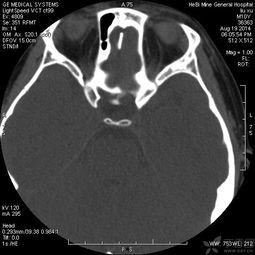

2. 定位:医生会使用影像学设备,如CT或MRI,来确定鼻窦的位置和脓液积聚的具体位置。